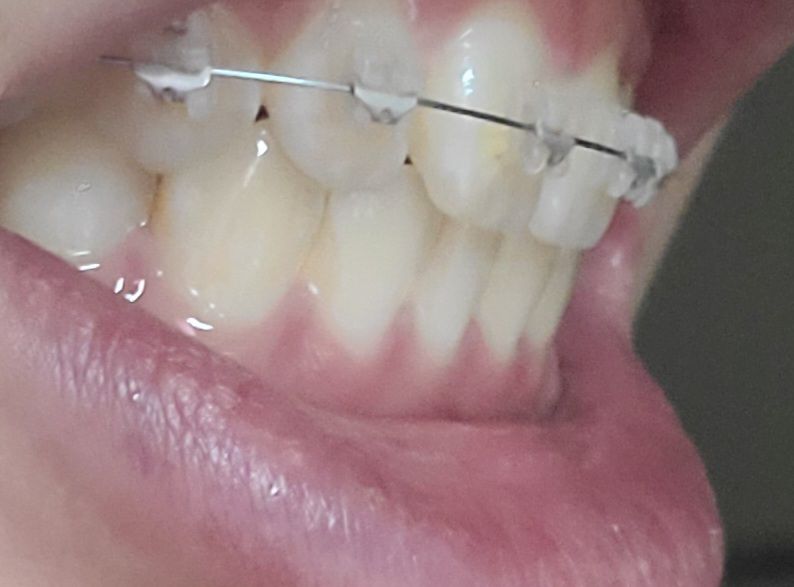

이를 앙 다물고 찍은 사진입니다

절단 교합은 상 하악 앞니가 정확히 일직선으로 맞물려야 합니다. 따라서 지금 정도로 절단교합이라고 하지 않습니다. 또한 음식 섭취 시 앞니는 음식을 간단히 끊는 용도이지 실제로는 어금니가 모든 역할을 합니다. 따라서 해당 치아가 현재로 맞물린다고 해서 마모되지 않습니다. 지금 정도는 교정 중이기 때문에 잘못되었다고 볼수도 없고 절단교합 및 이상이라고 하지 않습니다. 치료를 충실히 받으시길 바랍니다.

절단교합은 위아래 치아의 끝부분끼리 정확하게 맞닿는 상태를 의미합니다.

사진으로는 오른쪽은 절단교합이 아닌 정상교합이며, 왼쪽은 측절치가 애매하게 보이긴 합니다.

말그대로 절단교합은 앞니 끝과 아래니의 끝이 교합이 되는 상태를 말합니다. 사진상으로 보면 절단교합은 아니신거 같아요.